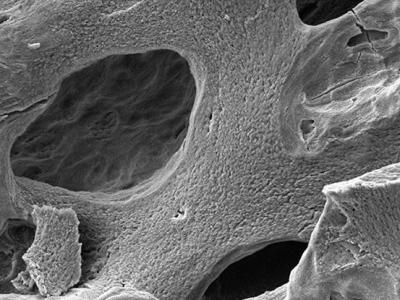

研究显示太空人在太空中会有剧烈的骨质流

研究显示太空人在太空中会有剧烈的骨质流失发生(神秘的地球uux.cn报道)据台北市立...